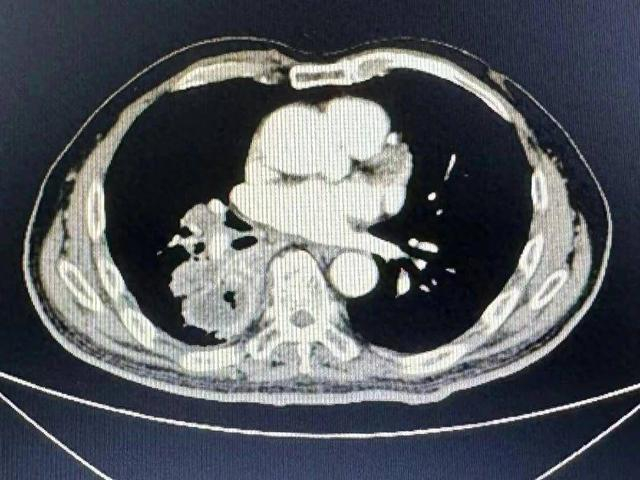

几近绝望的戴先生经人介绍,抱着最后一丝希望来到了南京市第二医院心胸外科,该科刘宏副主任接诊后,认真询问了病史,仔细阅片后判断,患者右侧脓胸伴毁损肺+反复咯血,手术是他唯一的出路,但手术难度很大。

“这类病人病程长,反复感染造成肺损毁,肺毁损导致肺解剖结构产生变化,比如肺动脉变薄变脆,支气管动脉扩张、迂曲、增生,还会有胸腔的广泛粘连。”刘宏介绍道,“肺损伤、萎缩,就像一个千疮百孔的烂苹果,不断的引起大咯血。手术难度大,很紧迫。国内少见,治疗非常棘手。”刘宏联合医院介入科、ICU、麻醉科、结核科等多学科,MDT诊疗团队讨论病情,确定了手术方案。在多学科的合力保障下,终于摘除了戴先生身上的这个定时炸弹。